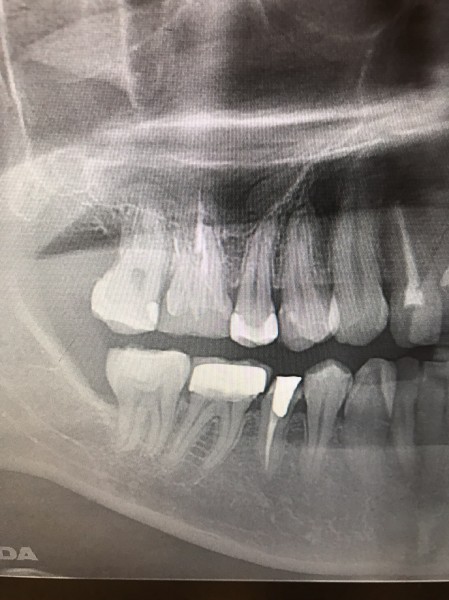

右の奥歯を過去に他院でインプラントをした方が、当院で左下や上の歯のインプラントをする為に転院してくださった患者様です。

インプラントは高額な治療ですが、どこの位置にどの角度で埋入するかが、とても大事というのがわかりやすかったので、患者様に投稿することをお願いして挙げさせていただきました。

インプラントを快適に長く使って頂くには、菌と力のコントロールが大事なのですが、前のものは位置が悪く、汚れも溜まりやすいし、咬む力も変な方向にかかってしまう仕上がりになっています。

被せ物のクオリティーもその歯科医院がどこの技工所にどのブランドで頼むかで全く変わってきます。

インプラントをご検討の方、すでに行った方は参考にしてください。